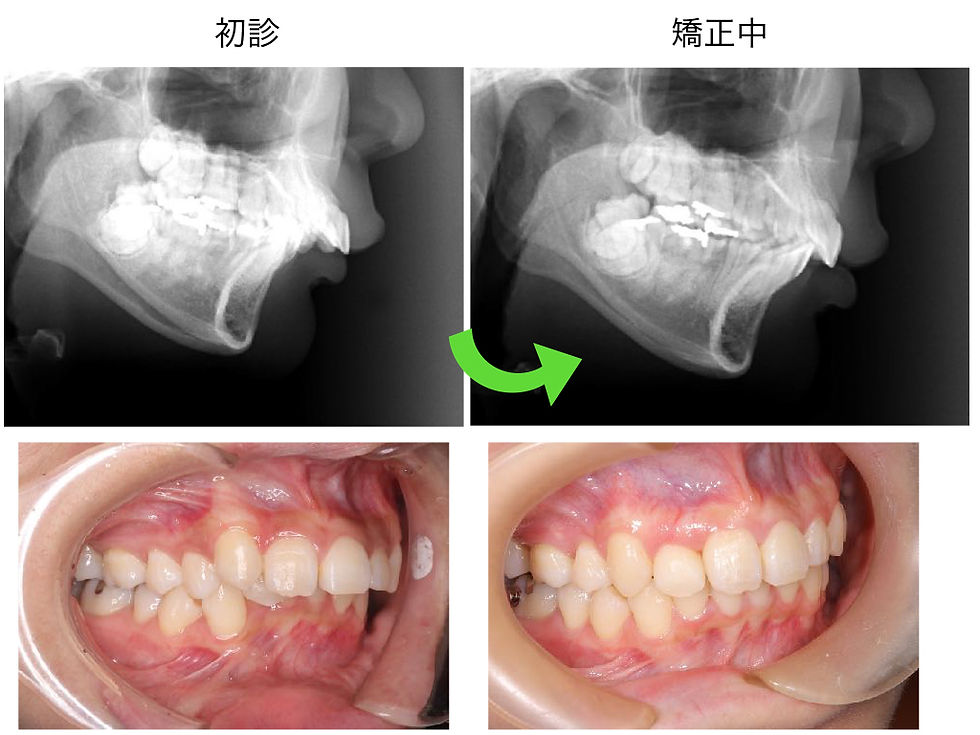

顎が後に下がっている。顔が曲がっている。不定愁訴がある。(20代・女性)

• 顎が後に下がっている

• 顔が曲がっているので矯正治療をしたい。

• 不定愁訴がある。

●治療内容

• 全顎矯正治療

• 矯正治療にて噛み合わせをあげた(咬合治療)

• 下顎の前方回転させた矯正治療

• 修復治療

初診時 矯正